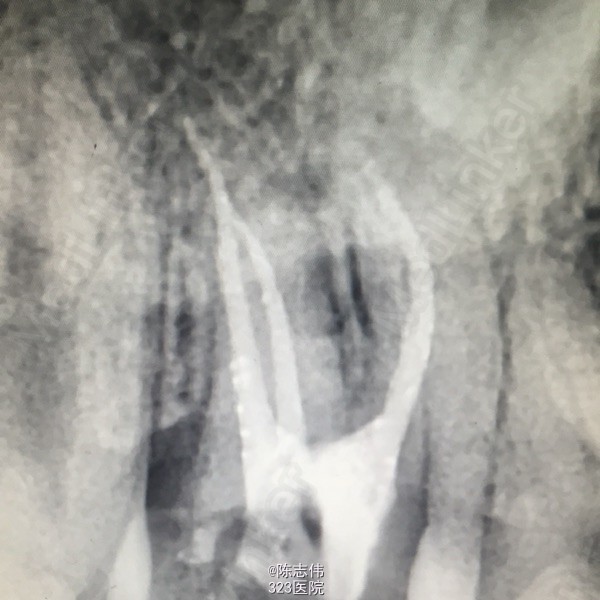

16近中颊部龋损,探深及龈下1mm,颌面白色充填物,冷(+) 松动(-) 叩(-) 17颊侧大面积龋损,缺损及龈下2mm,探(++) 叩(+) 冷(++) 松动(-) 45远中龋损,探(+) 冷(+) 松动(-) x线示:16龋损近髓 17,45缺损及髓,根尖无明显异常

印诊:16深龋 17,45慢性牙髓炎 建议:16充填治疗,若露髓则行RCT 17,45RCT+桩+冠 处理:局麻下16,17,45去龋,16龋净未露髓,清理干燥隔湿后垫底+3M树脂充填。17,45揭开髓室顶,丁香油棉开放,降颌